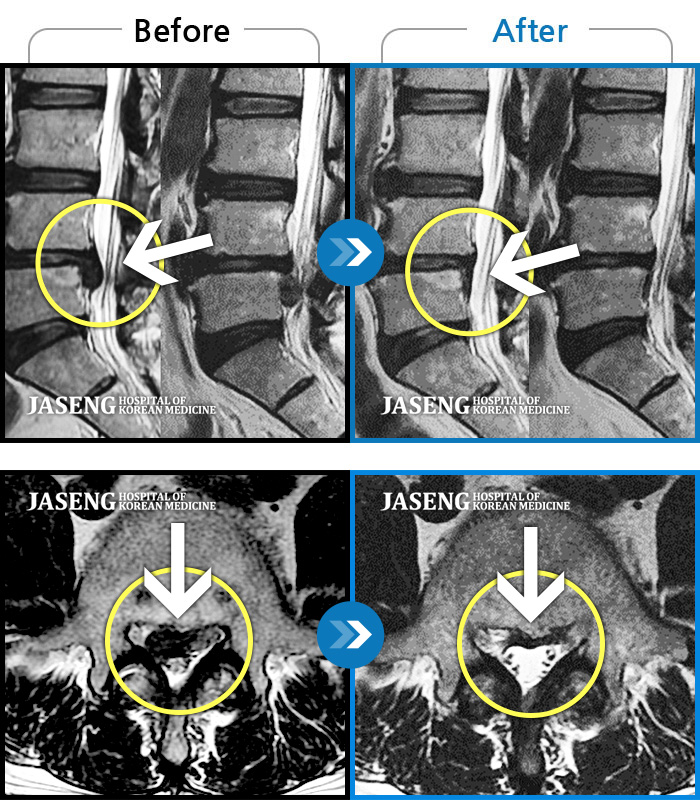

3. 두 번째 포인트 : ‘압박’이라는 표현의 강도

결과지에는 보통 이런 표현이 등장합니다.

- 경미한 압박

- 의미 있는 압박

- 신경근 압박 소견

여기서 환자가 꼭 알아야 할 점은,

‘압박’이라는 단어가 곧 수술을 의미하지는 않는다는 사실입니다.

중요한 질문은 이것입니다.

- 이 압박이 현재 증상과 연결되는가

- 압박이 점점 진행 중인가

- 기능 저하가 동반되고 있는가

MRI 결과는 증상과 함께 해석될 때 의미가 있습니다.